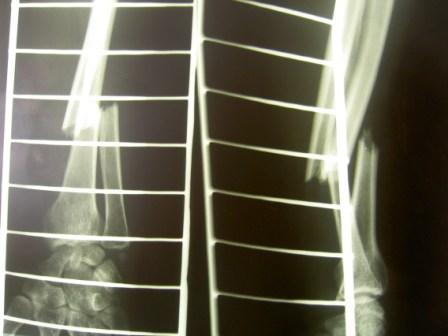

В анамнезе была попытка работать со сканером, не очень удобно, и для получения хорошего качества изображения необходим сканер хорошей разрешающей способности. и самое главное наилучшие результаты достигаются с применением сканеров проходящего света, а не отражающие (много помех), т.к. снимки тоже зачастую имеют артефакты и низкое качество. Последние 3 года испльзуем негатоскоп и цифровой аппарат Lumix Panasonik 7,0 мегапикселей. Снимаем в режиме макросъёмки без вспышки